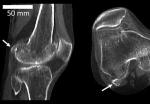

Подпорка для колена

Миллионы лет назад, на заре становления человеческого вида, из колена исчезла за ненадобностью маленькая косточка — флабелла. В последнее время ее снова начали находить.

Флабелла — одна из сесамовидных костей, располагающихся в сухожилиях. У животных она сформировалась примерно двести миллионов лет назад, чтобы придать прочности суставам, защитить сухожилие от повреждения при сильных нагрузках. Считается, что у человека эта кость повышает механическое сопротивление икроножной мышцы. Но зачем это нужно?

Ученые из Имперского колледжа Лондона (Великобритания) проанализировали 66 научных работ начиная с 1875 года, содержащих сведения о флабелле. Выяснилось, что она встречается в 36,8 процента случаев чаще у азиатов, жителей Океании и Южной Америки, а если брать в расчет половой признак, то предпочтительнее у мужчин. В целом в 2018 году эта кость распространена в человеческой популяции в 3,5 раза чаще, чем век назад — в 1918-м.

Рост флабеллы обусловлен генетически, но вот ее окостенение у всех происходит в разном возрасте и, возможно, зависит от механических причин. Чаще ее встречают у людей после 70 лет, но она может проявиться уже у 12-летних.

Обычно флабелла появляется в обеих коленях и служит причиной осложнений после хирургических операций по замене суставов. В имплантате ее присутствие не учитывают, и это вызывает боль при ходьбе. В итоге "лишнюю" кость приходится удалять.

Замечено также, что у людей с флабеллой нередко встречаются некоторые нейропатические заболевания, а риск остеоартрита колена увеличивается в два раза. Но что причина, а что следствие, пока неясно.

Флаббела — крошечная кость в колене — стала появляться у людей все чаще за последние 150 лет